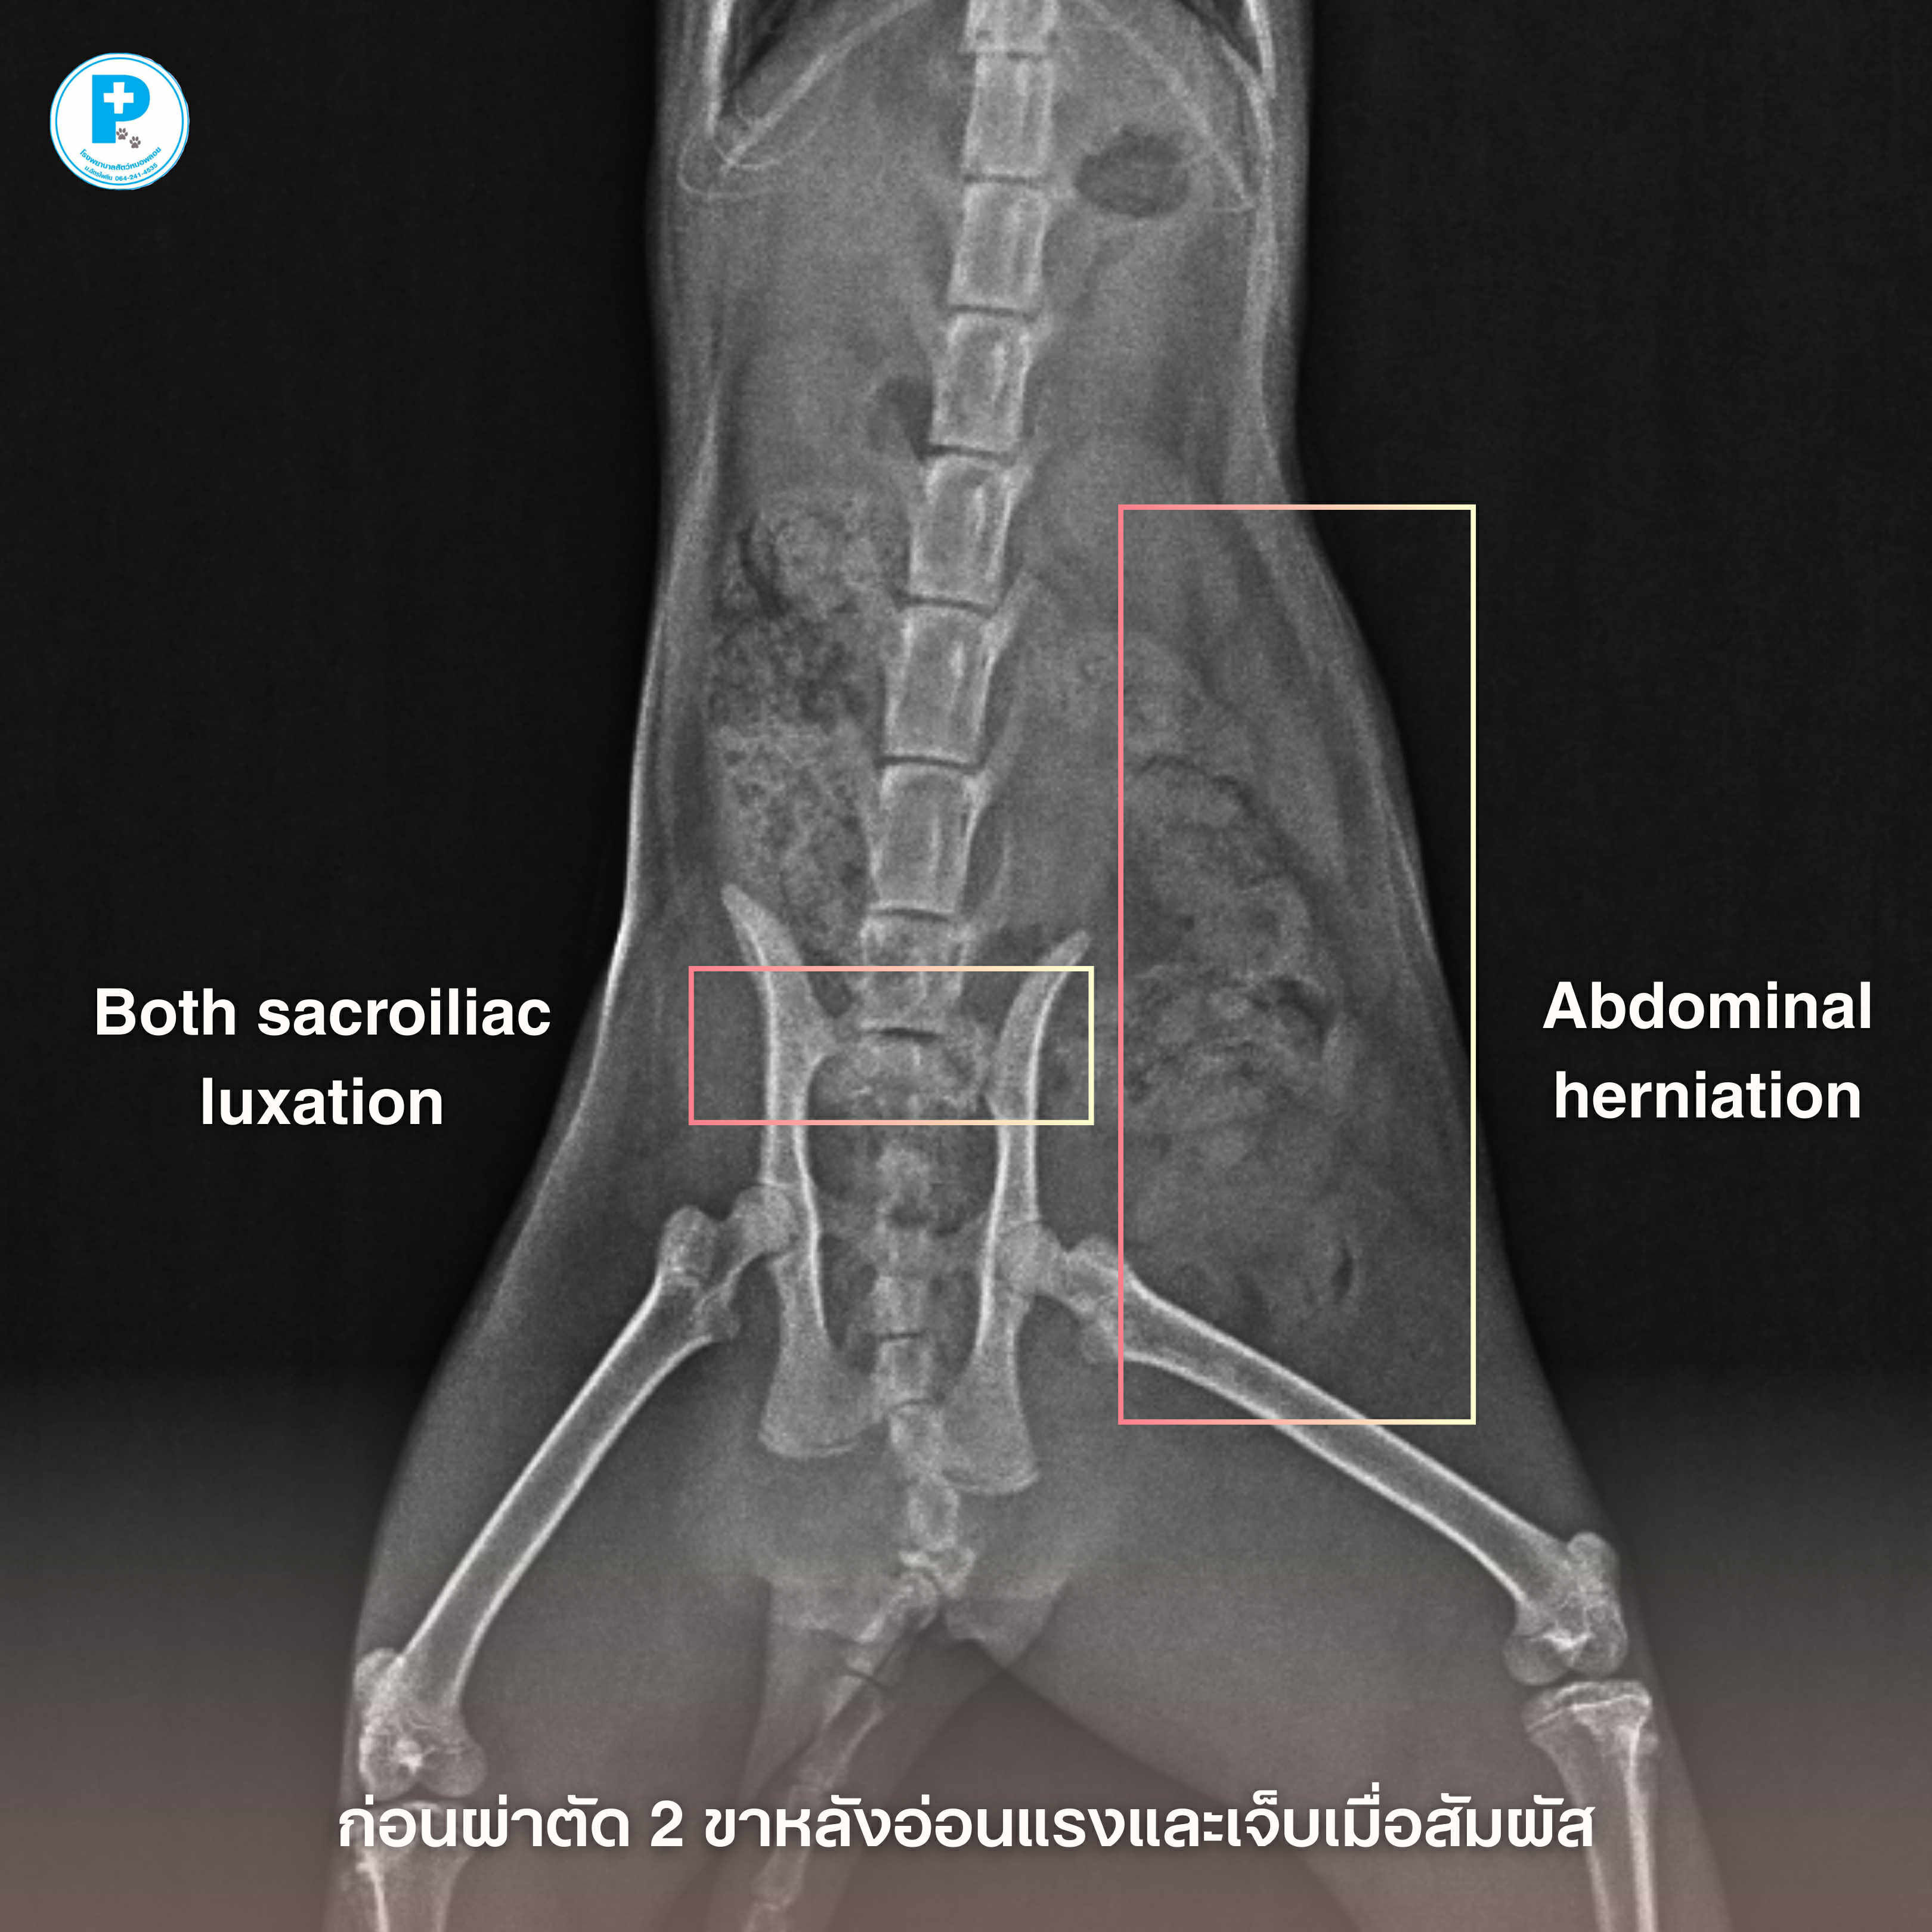

- น้องดำประสบอุบัติเหตุอย่างรุนแรง กระดูกเชิงกรานเคลื่อนทั้งสองข้าง (Both sacroiliac luxation) ร่วมกับภาวะไส้เลื่อนช่องท้อง (Abdominal herniation)

ก่อนผ่าตัด น้องดำมาที่รพส.ด้วยอาการ

• ขาหลังอ่อนแรง

• เจ็บเมื่อจับบริเวณเชิงกราน

• ผนังช่องท้องฉีกขาด ทำให้อวัยวะภายในเคลื่อนออกจากตำแหน่งปกติ

แนวทางการรักษา

ผ่าตัดจัดกระดูกด้วย Trans-iliac pin placement ร่วมกับ lag screw fixation

ซ่อมแซมผนังช่องท้อง (Abdominal hernia repair)การบาดเจ็บลักษณะนี้ หากปล่อยไว้อาจส่งผลต่อระบบประสาท การขับถ่าย และคุณภาพชีวิตระยะยาว

หลังผ่าตัด วางแผนทำกายภาพบำบัดเป็นลำดับ ควบคุมความเจ็บปวดอย่างใกล้ชิด ติดตามภาพรังสีประเมินการยึดติดของกระดูก

อุบัติเหตุอาจเกิดขึ้นได้เสมอ แต่การวินิจฉัยที่แม่นยำและการผ่าตัดที่เหมาะสม ช่วยให้เขากลับมายืนได้อีกครั้ง

ผ่าตัด: สพ.ญ.ณัฐฐ์ธวรรณ โสภิพันธ์ (หมอพลอย)

เรียบเรียง: น.สพ.นรภัทร โสภิพันธ์ (หมอพีท)